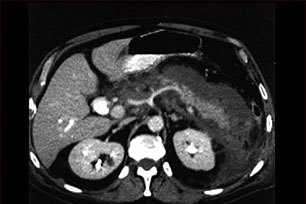

Данное изображение- это компьютерная томография верхней части брюшной полости, на которой четко диагностируется воспаление и отечность тканей поджелудочной железы, вызванной острой инфекцией (панкреатит).

- Компьютерная томография брюшной полости